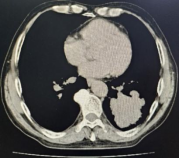

王先生因左侧下肢疼痛伴发凉一个月,前往ac米兰官网中文网站一院群力院区普外科就诊。然而,下肢血管术前常规肺部CT检查却带来了一个令人震惊的消息——左肺下叶存在一个巨大的肿瘤。在群力胸外科付凯教授的细致会诊和进一步的PETCT检查后,确认肿瘤虽大,但未出现其他脏器及淋巴结转移,手术治疗成为最佳选择。

正当王先生准备接受左肺下叶肺癌根治术时,术前心电图却显示他存在频发的室性早搏和二联律。出于对患者生命安全的慎重考量,手术被紧急暂停。经过冠脉CTA和动态心电图检查,王先生的冠脉并无明显异常,但24小时室早次数高达43000次,手术风险极大。

在射频消融治疗成功后,付凯教授为王先生安排左肺下叶肺癌根治术。面对巨大的肺部肿瘤,微创手术实施难度极大,但考虑到患者的综合情况,微创手术无疑是创伤最小、术后并发症最少的手术方案。经过两个多小时的艰苦奋战,王先生的手术取得了圆满成功。左肺下叶及肿瘤在胸腔镜的微创操作下被完整切除,并在保护套中分块取出。